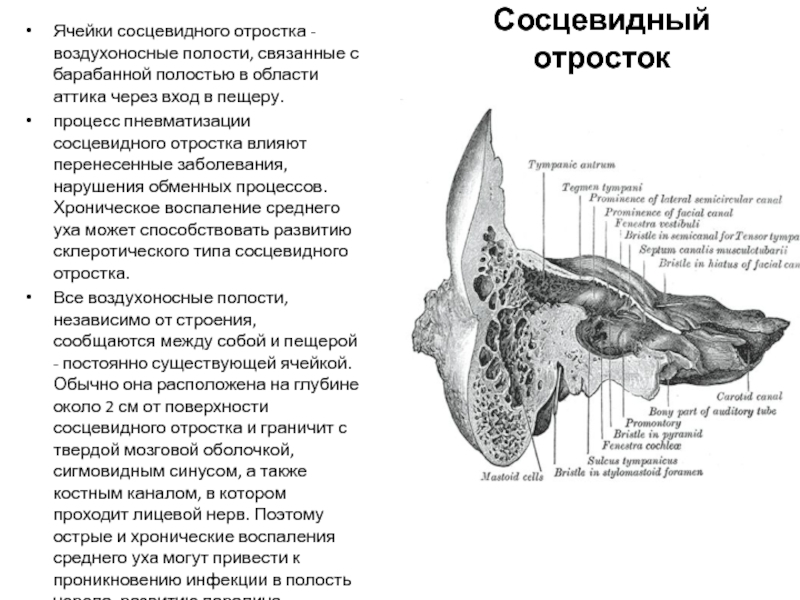

КТ анатомия сосцевидного отростка: особенности и показания